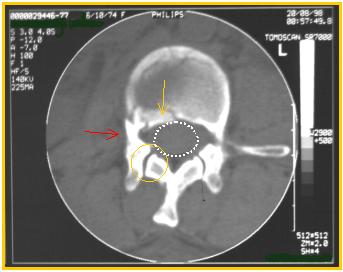

| Sezioni TAC della parte superiore del soma di L2 del caso precedente. Si osserva una frattura del muro posteriore con un piccolo frammento lievemente protruso all'interno del canale vertebrale (freccia gialla) ma senza che esso provochi compressioni a livello del midollo spinale (evidenziato dall'ovale tratteggiato). Il peduncolo di destra (freccia rossa) è integro così come lo è il processo articolare (cerchio giallo). |  |